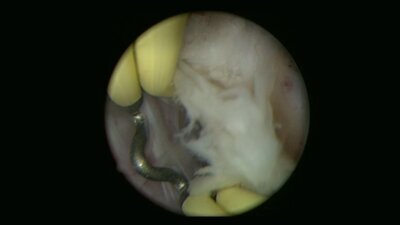

Операции на простате